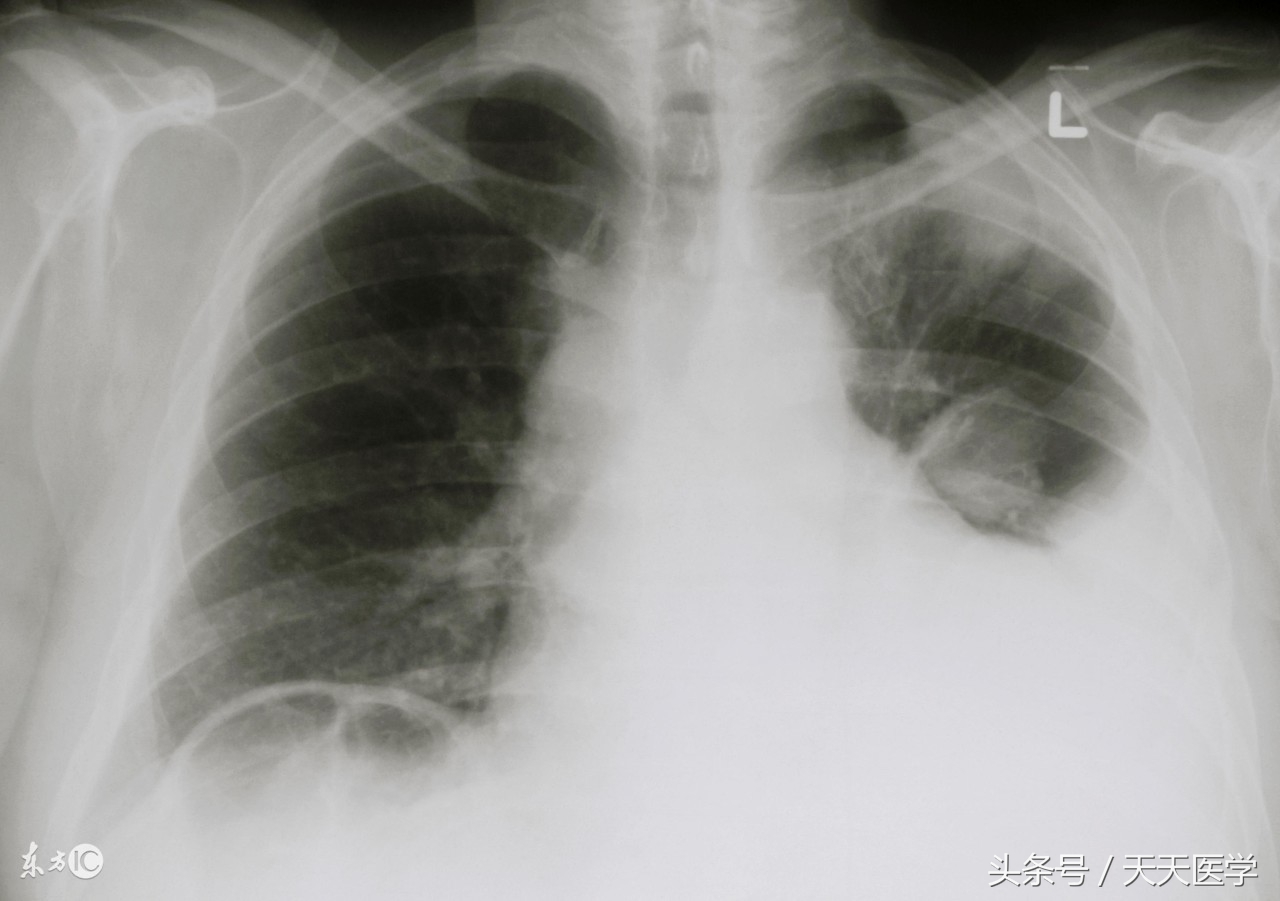

3.辅助检查:影像学检查显示胸腔大片高密度阴影改变。

(5)影像学检查:胸部X线片、胸部B超、胸部CT;

2.复查胸部X线或CT,提示胸腔积液基本消失;